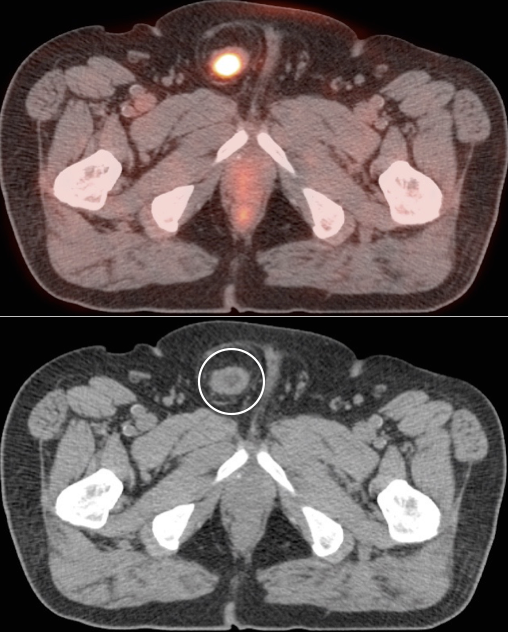

Bladder Hernia

While the CT appearance of this finding should never be missed, its striking PET appearance has led more than one PET/CT reader astray.

Usually, the supero-lateral margin of the bladder will be seen partially entering the inguinal canal. Occasionally, a significant segment of the bladder may extend deep into the hernia defect.

Caveat: Never be duped by an unusual focus of intense metabolic activity anywhere in the body. Always rule out every possible non-neoplastic explanation before raising the specter of cancer.